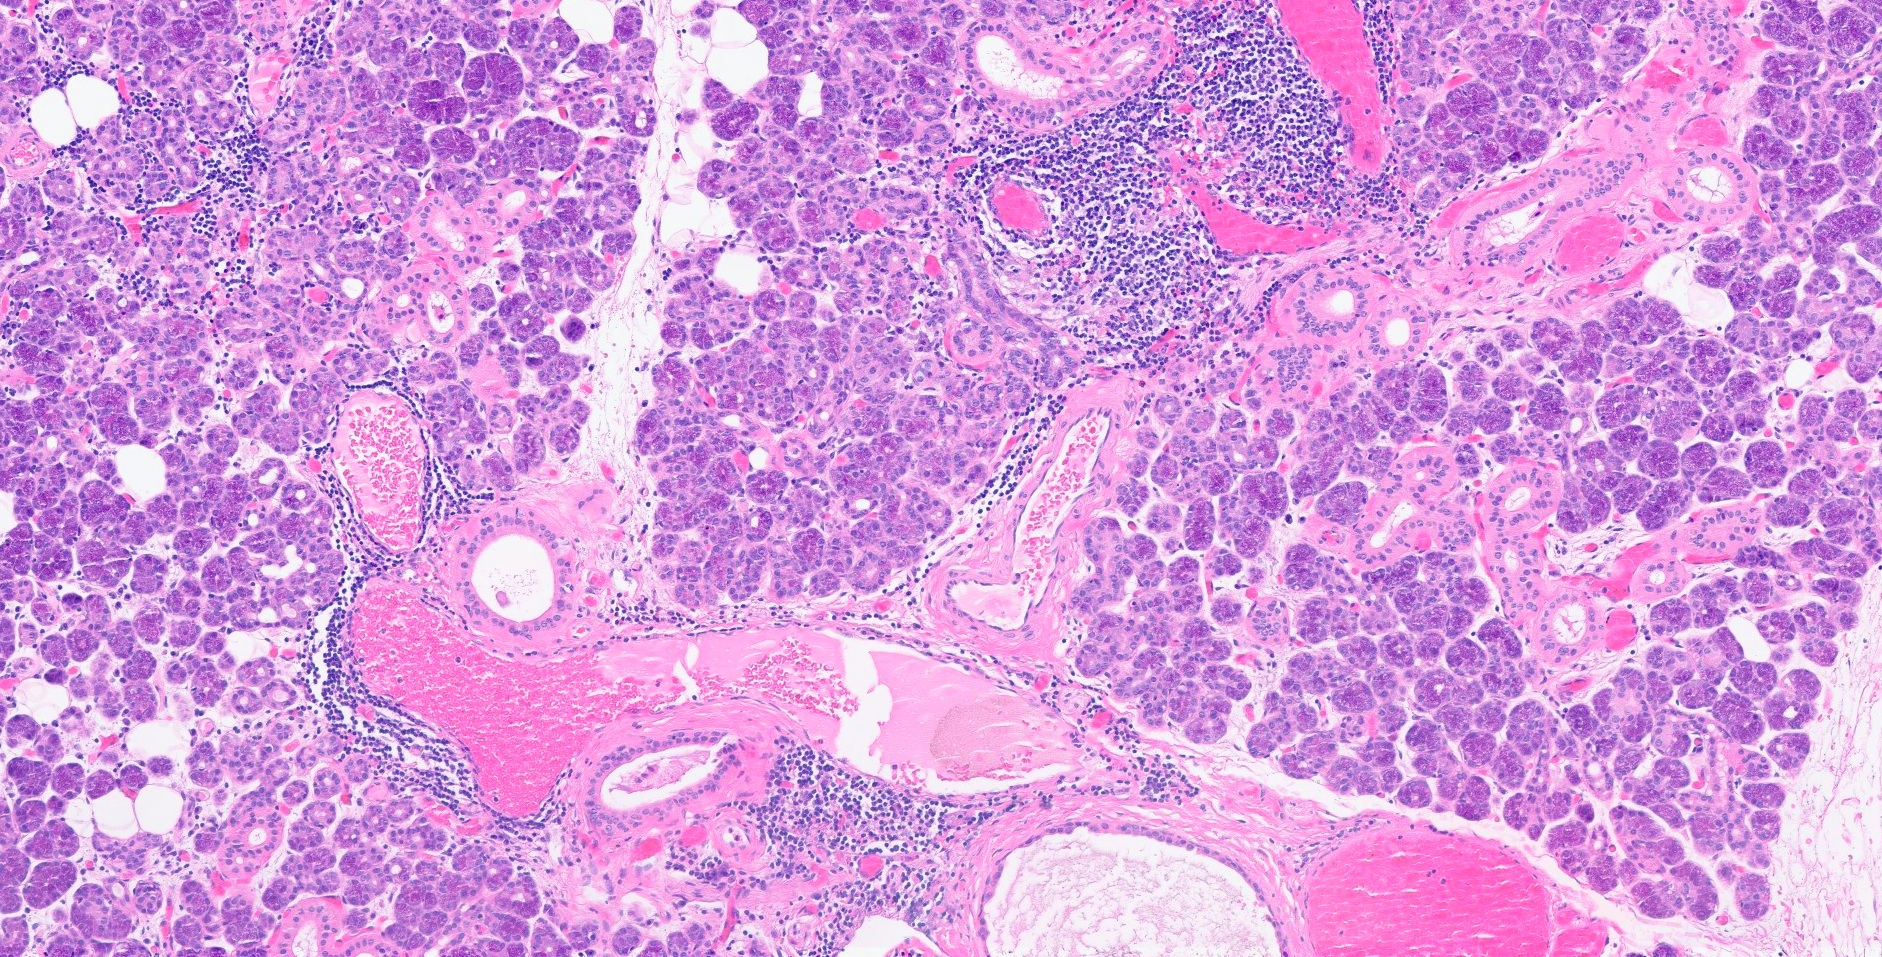

Outcome and follow-up. The patient’s submandibular gland was successfully removed and the sialolith was extracted. The surgical pathology demonstrated left submandibular excision with sialadenitis and sialolithiasis (Figures 3 and 4). Pathology was negative for neoplasm in the gland, which measured at 29 mm by 37 mm by 17 mm. Findings for the sialolith showed a single tan-white friable calculus that is present within a dilated ductal structure. The sialolith measures 11 mm in greatest dimension.

Figure 4. Fibrosis and chronic inflammation surrounding intercalated and interlobular ducts (H&E, original magnification × 10). Intercalated and interlobular ducts are involved by periductal fibrosis and periductal chronic lymphocytic infiltrate, consistent with focal sialadenitis. The remainder of the salivary gland demonstrates unremarkable serous and mucinous acini surrounded by fibrotic stroma with chronic inflammation.